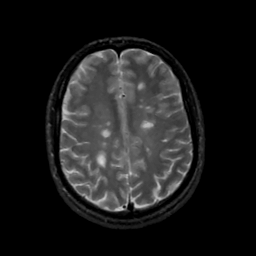

MR Study #12, May 12, 1991 -- Slice #35